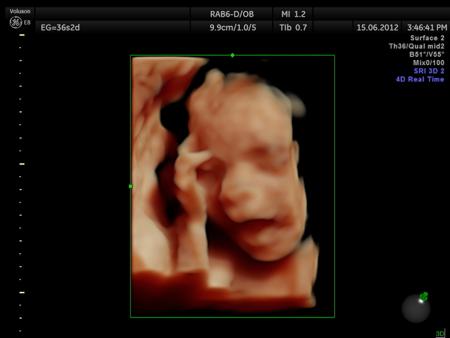

La ecografía 4D HD/5D consiste en la adquisición y presentación continúa de volúmenes. La denominación de la técnica obedece a que hay cuatro dimensiones involucradas: ancho, largo, profundidad y tiempo.

Si bien la Ecografía 4D HD/5D puede realizarse en cualquier etapa del embarazo, recomendamos realizarla entre las semanas 24 a 32 de gestación ya que se pueden observar rasgos bien definidos en el bebe.

Fotografías de ecografías 4D HD/5D

Haga click sobre las imágenes para ampliar